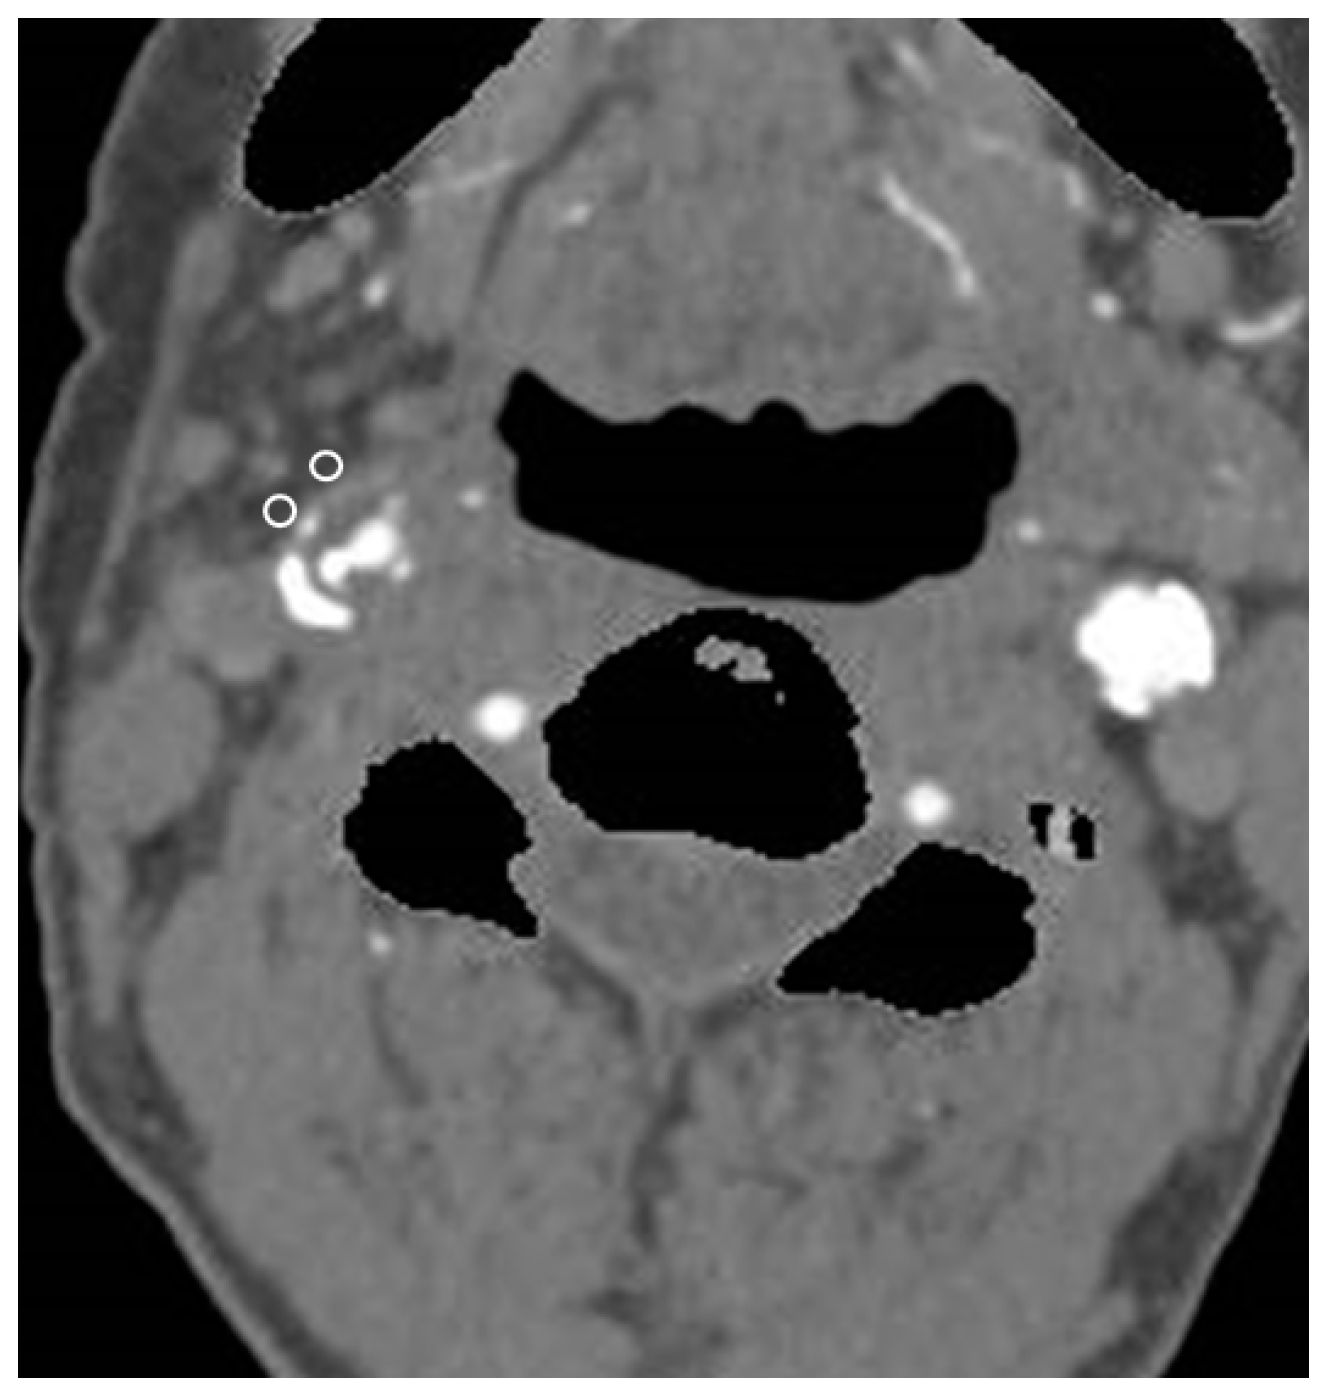

2.3. CTA and Pericarotid Fat Density Measurement